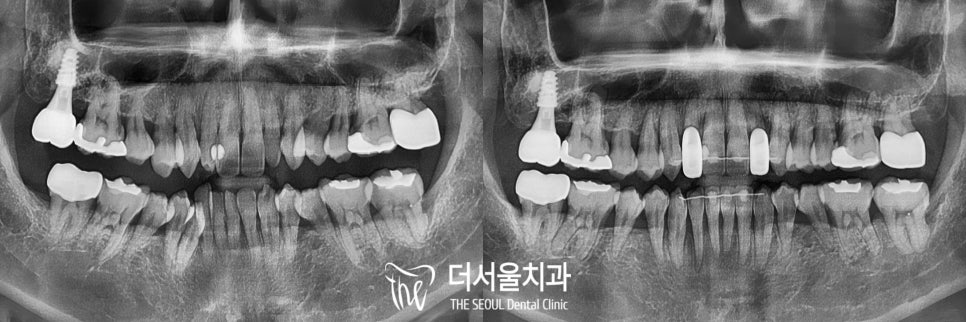

1. 초진

“오른쪽 아래 덧니가 점점 더 심해지는 거 같아요.

이가 틀어져있으니까 음식도 더 많이 끼고

아무리 양치해도 관리가 힘드네요.”

4. 마무리

치료가 어느 정도 끝나가면

쉐이드 가이드를 통해

환자의 주변치와 비슷한 색상을 골라

크라운을 제작합니다.

크라운은 다른 재료에 비해

탈락률이나 부작용이 적으니 걱정하지 마세요.

앞니이기에 크기, 마모도, 투명도를 전부 고려하여

균형감 있는 치아로

왜소치가 개선된 모습을 확인할 수 있습니다.

전체적으로 보았을 때 깔끔하게 정리된 모습이며,

주변 이들과도 자연스럽네요.

교정까지 함께 진행된 증례이기에

더욱더 심미적으로 보입니다 ^^

치료기간 2021.05.12~2022.01.20